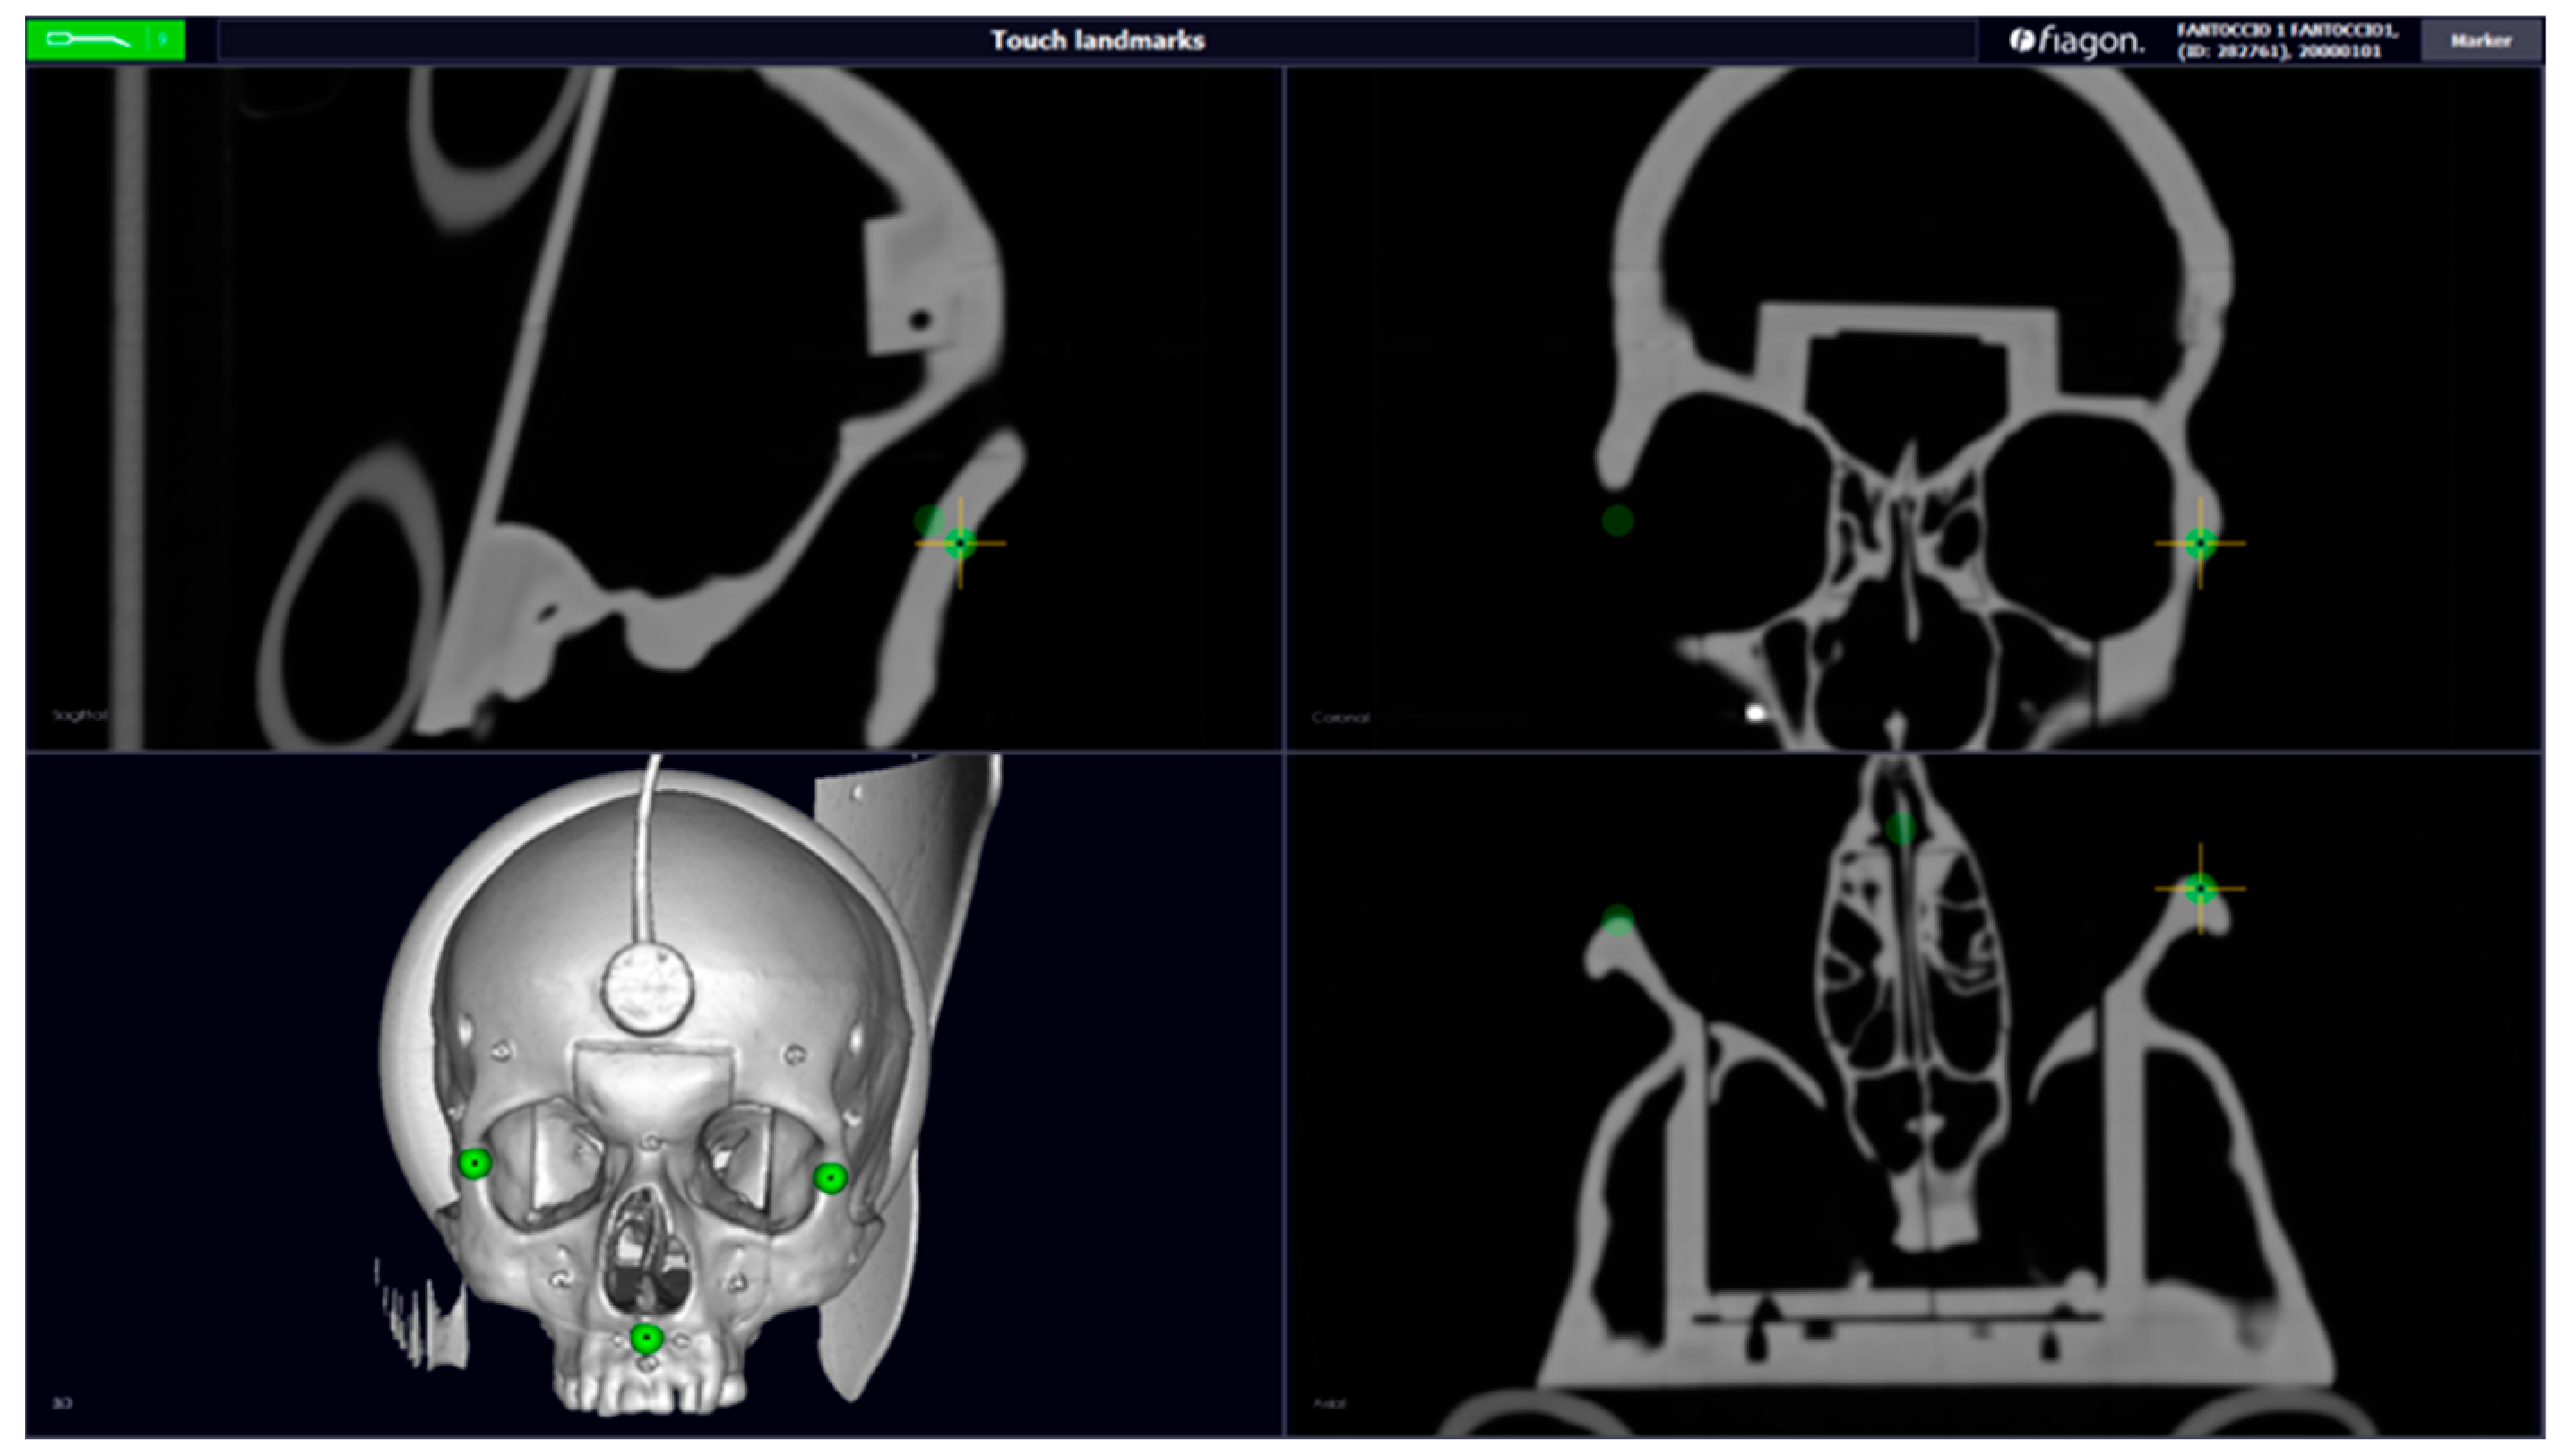

Today, surgical navigation is one of the most reliable technologies; it continues to transform surgical interventions into safer and less invasive procedures. In surgery, navigation has stimulated technical progress in both exploratory and interventional procedures in those areas with limited access. The surgeon can know, in real time, where he is moving with the instrument and so can be as accurate as possible. For this reason, the first use of surgical locators is in neurosurgery and maxillofacial surgery, where accuracy must be sub-millimeter [1]. We can classify surgical navigators according to the location technology on which they are based. These systems include sensors and emitters of various types (optical, electromagnetic, etc.) that provide data on the position and orientation of an element in space. The purpose of all localizers is to know, in real time, the position of surgical instruments in the operating space and to make everything visible on a monitor. Pre-operative images will also be present on this monitor [2]. In addition to purely anatomical orientation, intraoperative navigation is also used as a measuring instrument and provides detailed information to surgeons [3]. The position and orientation of surgical instruments are determined by the direct visibility of the surgical field [4]. This study aims to improve the result of the operation by ensuring greater precision and less invasiveness, therefore resulting in fewer post-operative risks for the patient. In the Fiagon neuro navigator (Fiagon GmbH, Hennigsdorf, Germany), the sensor is placed on the patient’s forehead with a sticker, which allows you to calibrate the device. Below is an alternative method of positioning the sensor for maxillofacial surgery, whilst always trying to maintain the accuracy of the navigator. The device developed is an orthodontic bite support with cylindrical support in which we placed the electromagnetic sensor. The bite was designed on a specific phantom, on which we performed all the tests to evaluate its accuracy. To do this, it was necessary to perform a phantom’s CT scan, and we created a dental device using CAD software (AutoCAD LT 2018) (Figure 1).

Figure 1. CT scanning (axial, sagittal, coronal, and 3D) with the dental device, created using CAD software. Green points—Fiducal Landmarks for calibration (maxillo malar suture and anterior nasal spine).